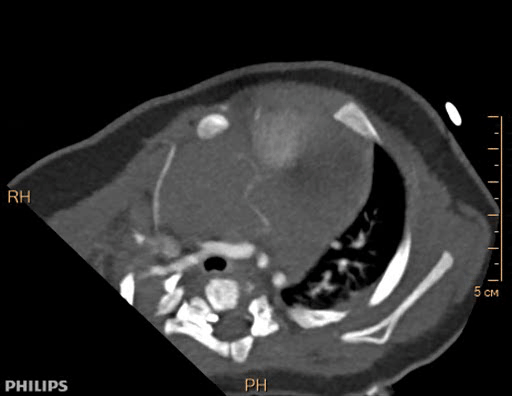

Выполняется трансторакольное ЭХОКГ исследование, которое позволяет заподозрить локализацию и размер опухоли, ее соотношение с другими анатомическими структурами сердца.